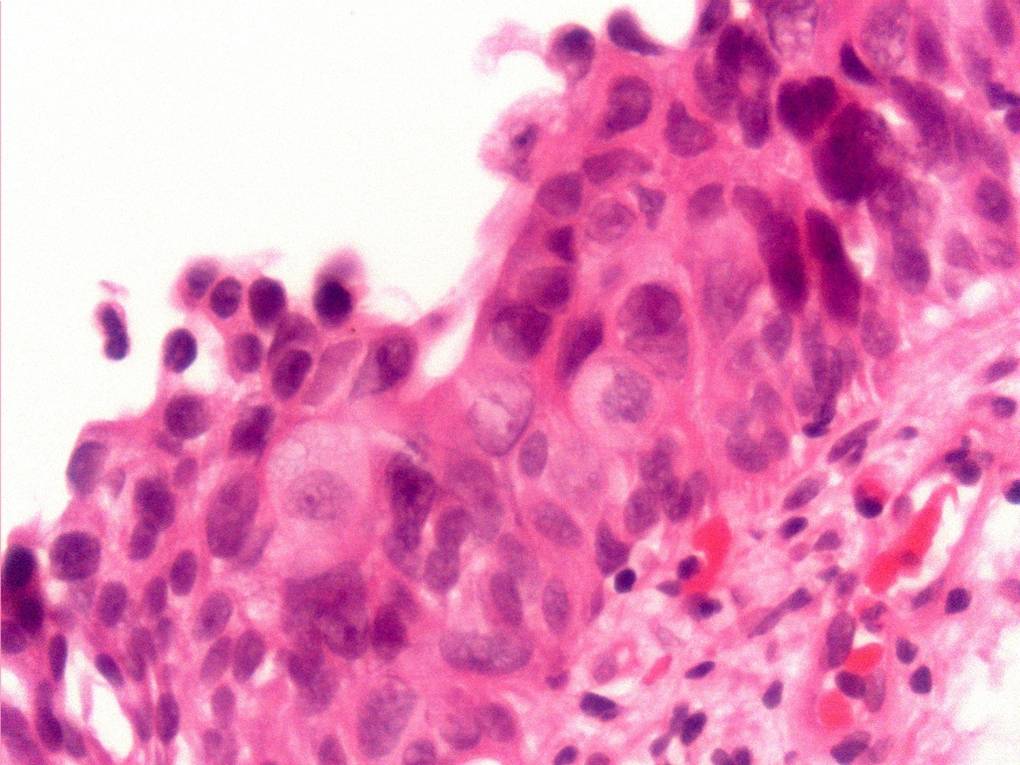

Bladder Flat Lesions

Case ID: 73